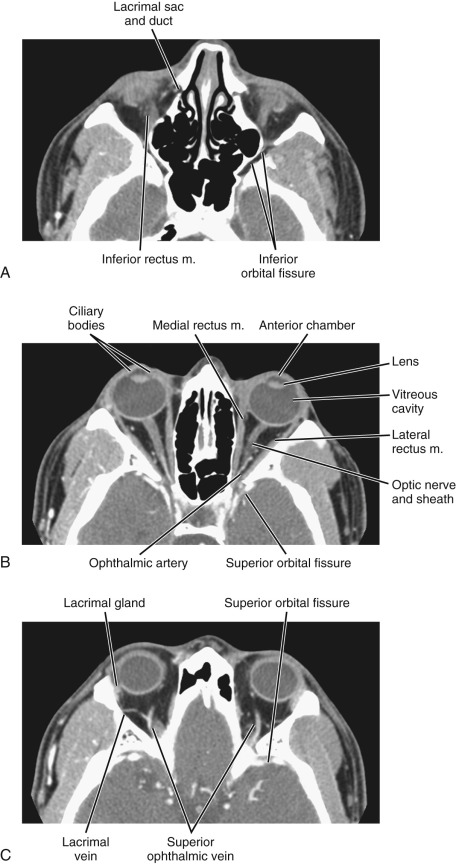

A CT orbit scan is a diagnostic imaging procedure specifically designed to examine the orbits, which are the bony cavities in the skull that house the eyes and their associated structures. This scan utilizes computed tomography (CT) technology to produce detailed cross-sectional images of the orbits, including the eye sockets, optic nerves, extraocular muscles, and surrounding soft tissues.

The primary aim of a CT orbit scan is to evaluate conditions affecting the eyes and surrounding areas. It is commonly used to diagnose and assess a variety of issues such as orbital fractures resulting from trauma, tumors or masses within the orbit, and inflammatory or infectious conditions like orbital cellulitis. The scan can also help in identifying abnormalities in the optic nerves and assessing conditions that might impact vision or eye movement.

The procedure involves the use of x-rays, which are processed by a computer to create detailed images of the orbit. These images provide valuable information for diagnosing disorders, planning treatments, and guiding surgical interventions. For instance, it can be instrumental in pre-surgical planning for orbital surgeries or in monitoring the progress of certain conditions.